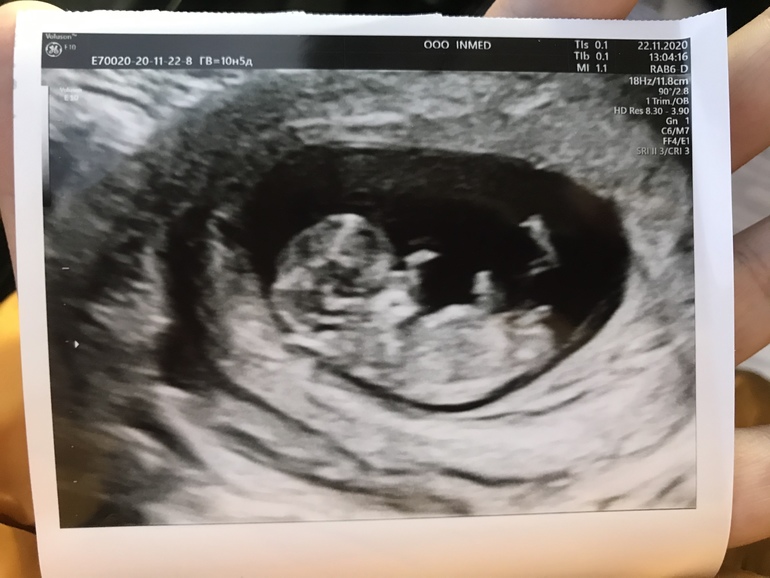

УЗИ в 10,5. Половой бугорок?

КТР - 41 мм с копейками, ЧСС - 173 удара, хорион по передней стенке. Срок по месячным 10,5, по КТР сказали 11,1 😅

Дали фотку) главный специалист на бб по половым бугоркам Анна 😉 говорит, что девочка.